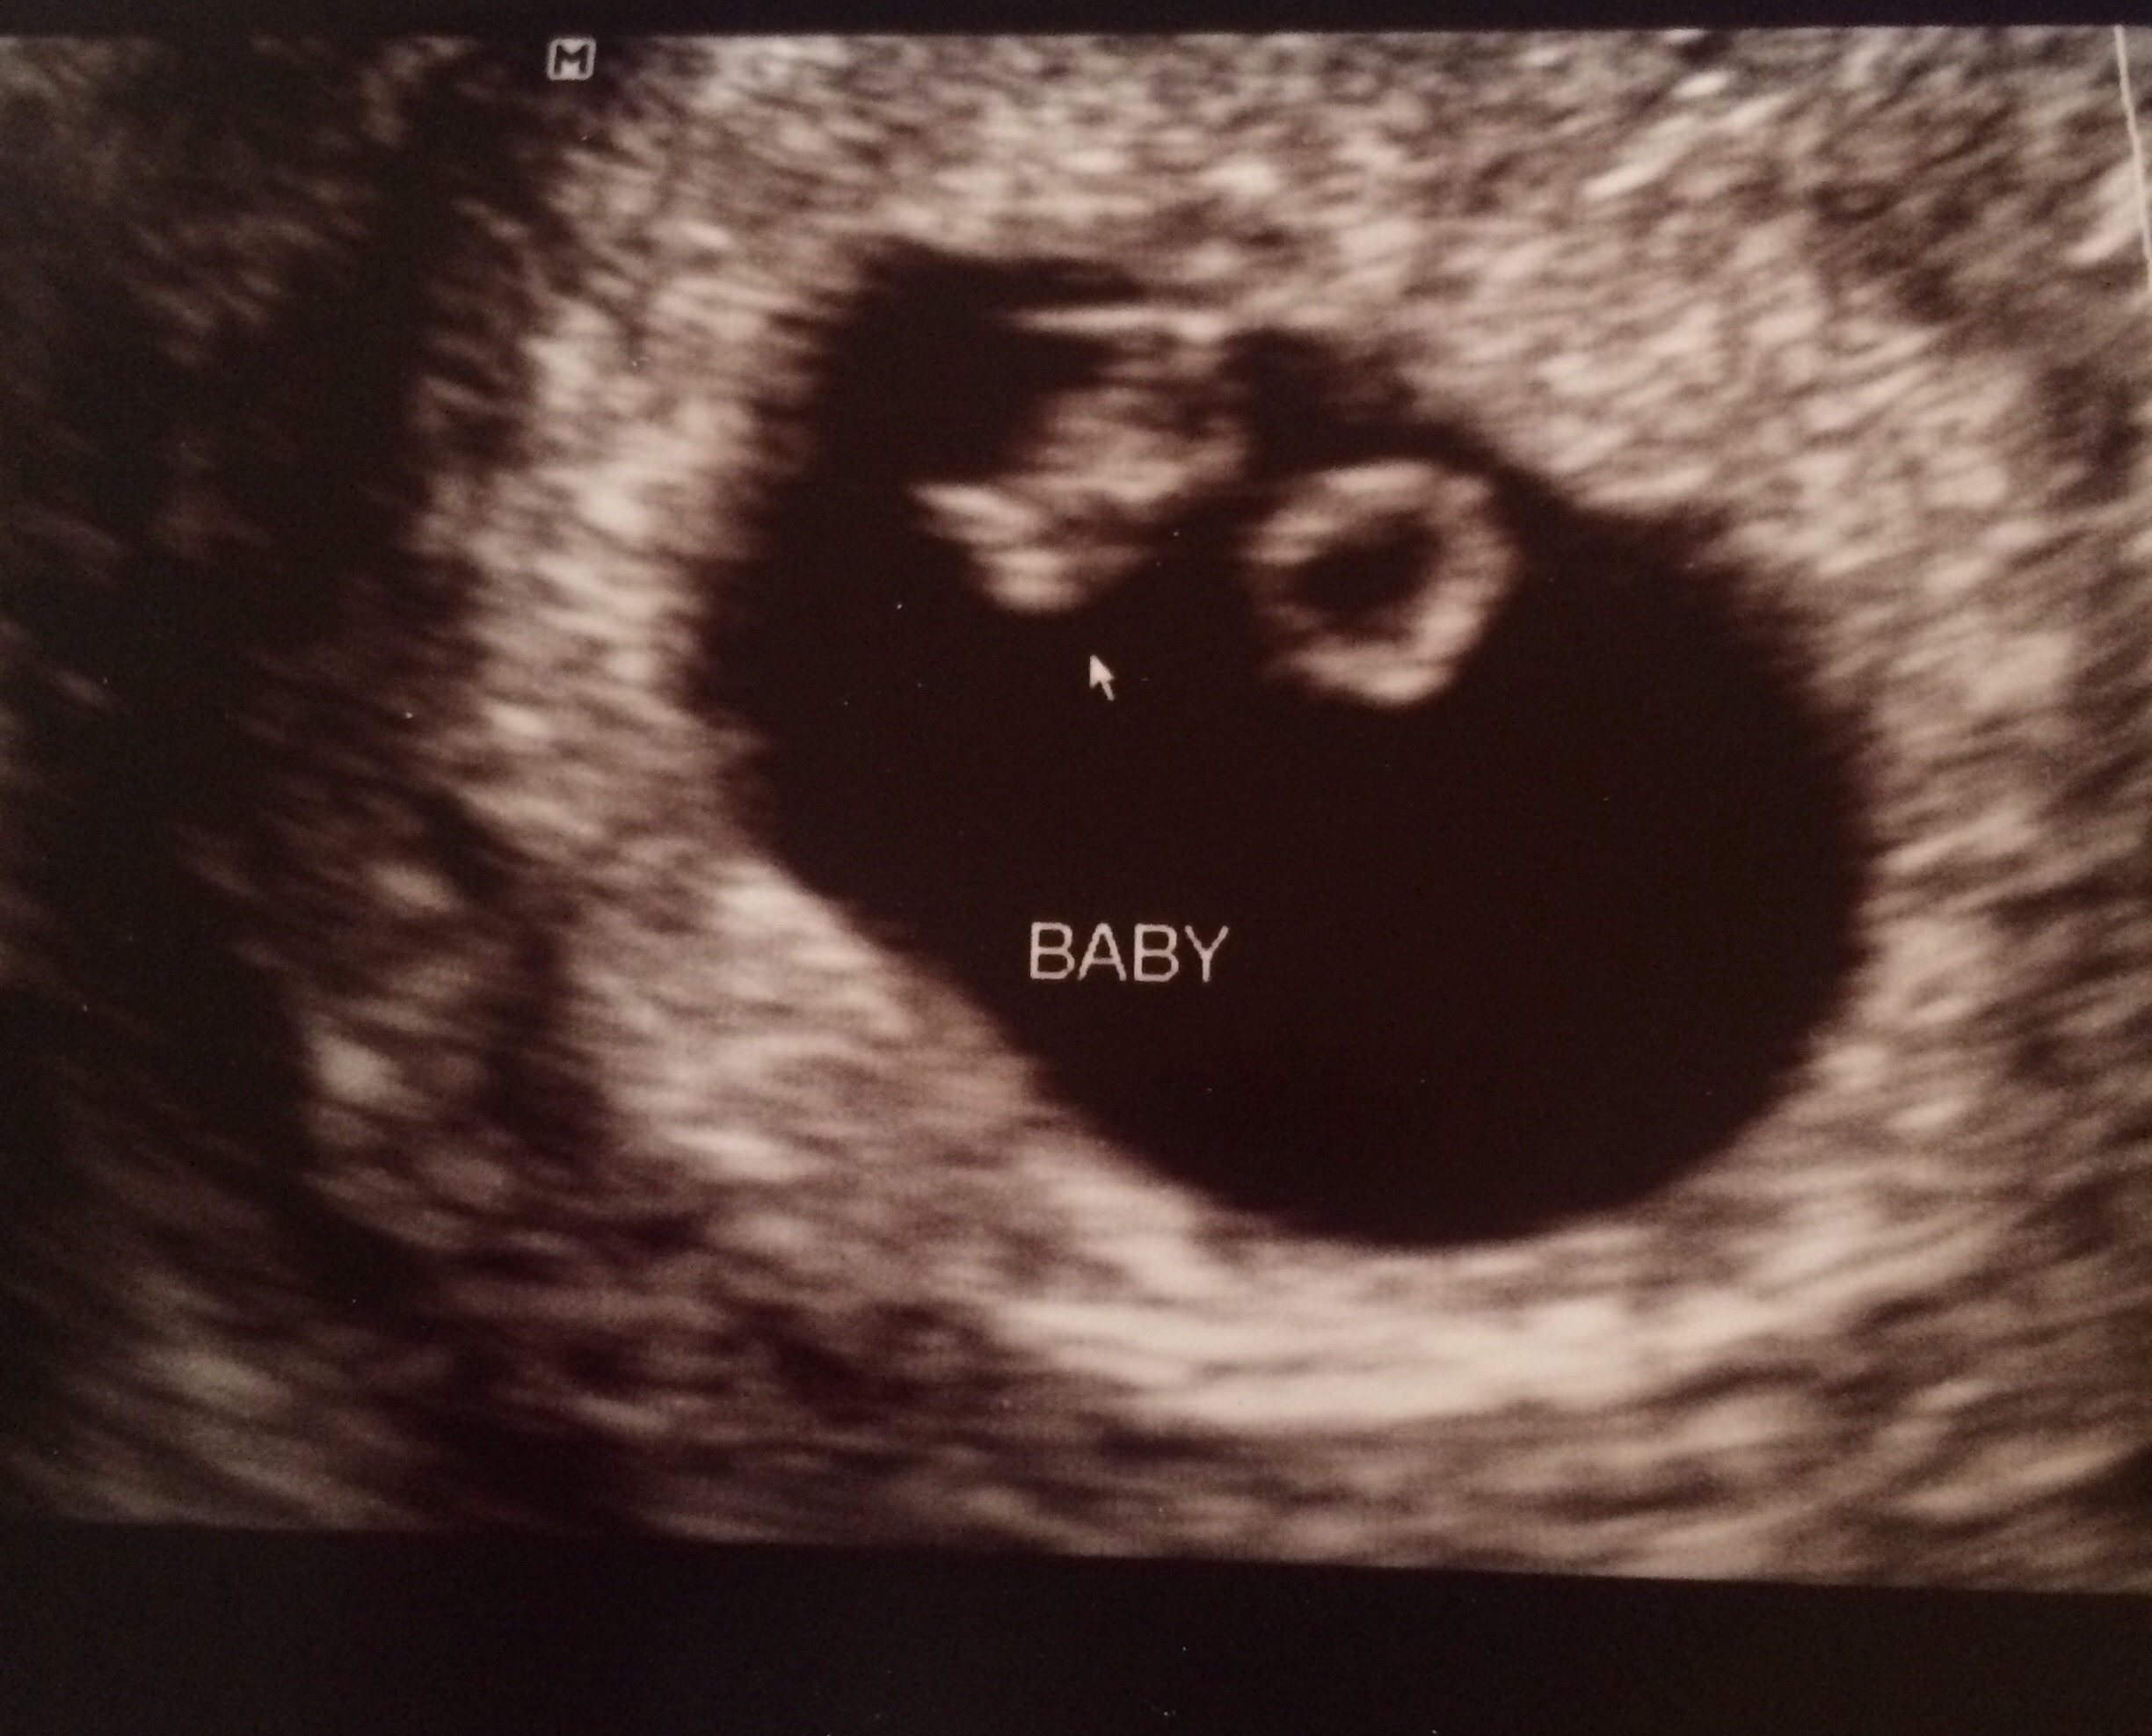

I know it is still early but some of you have already had your first ultrasound.

Feel free to share your picture(s) as you have them done!

Also be sure to include any information related to the U/S that you want to share with the group (how many weeks, heart rate, type of U/S, etc.).

125 bpm

Thought i was further along.. Had a early scan because i had an mc 2 months ago.

Next week follow up to see if she/he has grown. Nervous!

ETA: HR 130